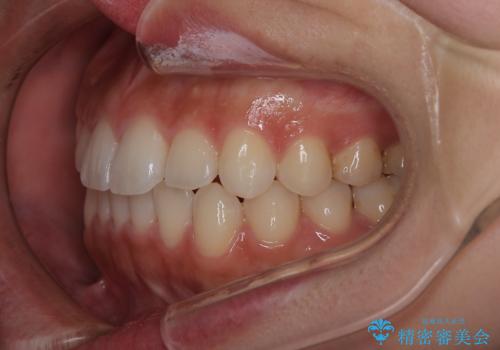

- 前歯の叢生を主訴に来院されました。非抜歯でインビザラインで治療をしました。

叢生はIPRをし、並べました。この患者様はオープンバイトだったため歯を並べる過程でかみ合わせも治しました。